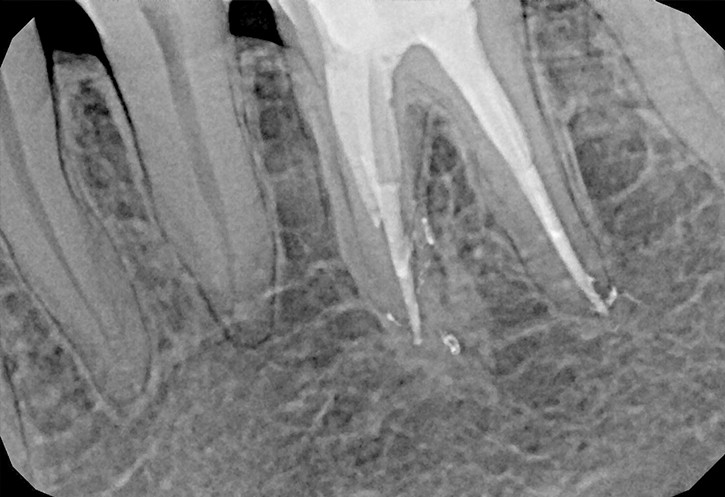

W przypadku zaawansowanych postaci zapaleń miazgi oraz zapalenia tkanek okołowierzchołkowych obraz radiologiczny jest warunkiem rozpoznania. W takiej sytuacji standardem diagnostycznym są zdjęcia przylegające zęba, często wykonywane przy użyciu radiowizjografii na fotelu stomatologicznym w trakcie leczenia zęba. Przydatne jest również badanie RTG OPG pantomograficzne, które pokazuje w dwuwymiarowym obrazie zarówno uzębienie, jak i cały układ kostny szczęki oraz żuchwy.

Stożkowa tomografia komputerowa CBCT, ze względu na dokładne, trójwymiarowe obrazowanie 3D, bez zniekształceń ukazuje szczegóły anatomii zęba oraz okolicznych tkanek, wyjaśniając nierzadko problemy niemożliwe do zdiagnozowania standardowymi metodami.

Na podstawie zdjęcia rentgenowskiego określa się kształt i długość kanału bądź za pomocą specjalnego urządzenia mierzy się jego długość. Potem lekarz otwiera wejścia do kanału, chroniąc ząb koferdamem, czyli specjalną gumą, zapewniającą sterylność oraz chroniącą przed środkami chemicznymi służącymi do oczyszczania kanału. Używa się do tego zarówno specjalistycznego sprzętu, jak i nowoczesnych mikroskopów, pozwalających na uzyskanie dokładnego obrazu leczonego zęba. Ostatnią czynnością jest wypełnienie materiałem światłoutwardzalnym i zabezpieczenie zęba przed dostaniem się i rozwojem bakterii mogących wywołać wtórny stan zapalny.

By uniknąć niedokładności leczenia, oprócz sumiennego wykonania procedur należy diagnostycznie kontrolować każdy etap leczniczy przy użyciu rtg. Szansą dla niedokładnie wypełnionego kanałowo zęba jest jego powtórne leczenie endodontyczne, zwane REENDO.

Konieczność powtórnego leczenia endodontycznego może zaistnieć w sytuacji, gdy kanały zęba nie zostały wypełnione do ich anatomicznego wierzchołka lub w trakcie leczenia doszło do złamania i pozostawienia ułamanego narzędzia w świetle kanału korzeniowego. O konieczności powtórnego leczenia endodontycznego może również zadecydować zmiana zapalna przy wierzchołku korzenia, która jest widoczna jedynie na obrazie kontrolnego zdjęcia rtg.